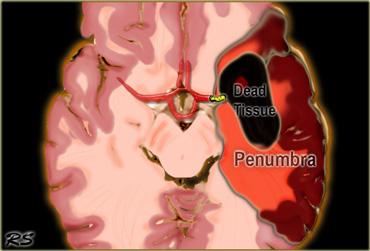

Vùng tranh tối tranh sáng (Penumbra): Tắc động mạch não giữa (MCA) với mô não tổn thương không hồi phục hoặc đã hoại tử màu đen và mô não có nguy cơ hay vùng tranh tối tranh sáng màu đỏ.